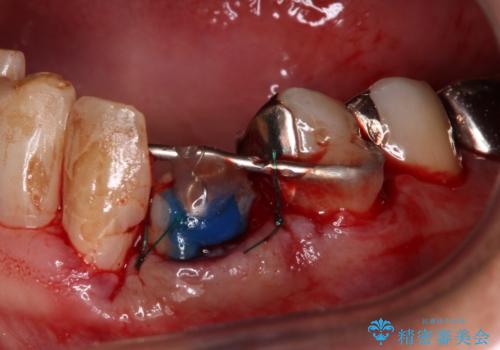

麻酔下で歯肉を開いて診察をしたところ、唇側の歯肉縁下に深く歯が欠けている状態でした。

当該歯である犬歯は歯根が長く、安易に抜歯することはおすすめできないため、まずは部分矯正により歯根を引っ張り出し、その後歯周外科処置により歯槽骨や歯肉の状態を整え、最終的にはオールセラミッククラウンにて補綴治療を行うこととしました。